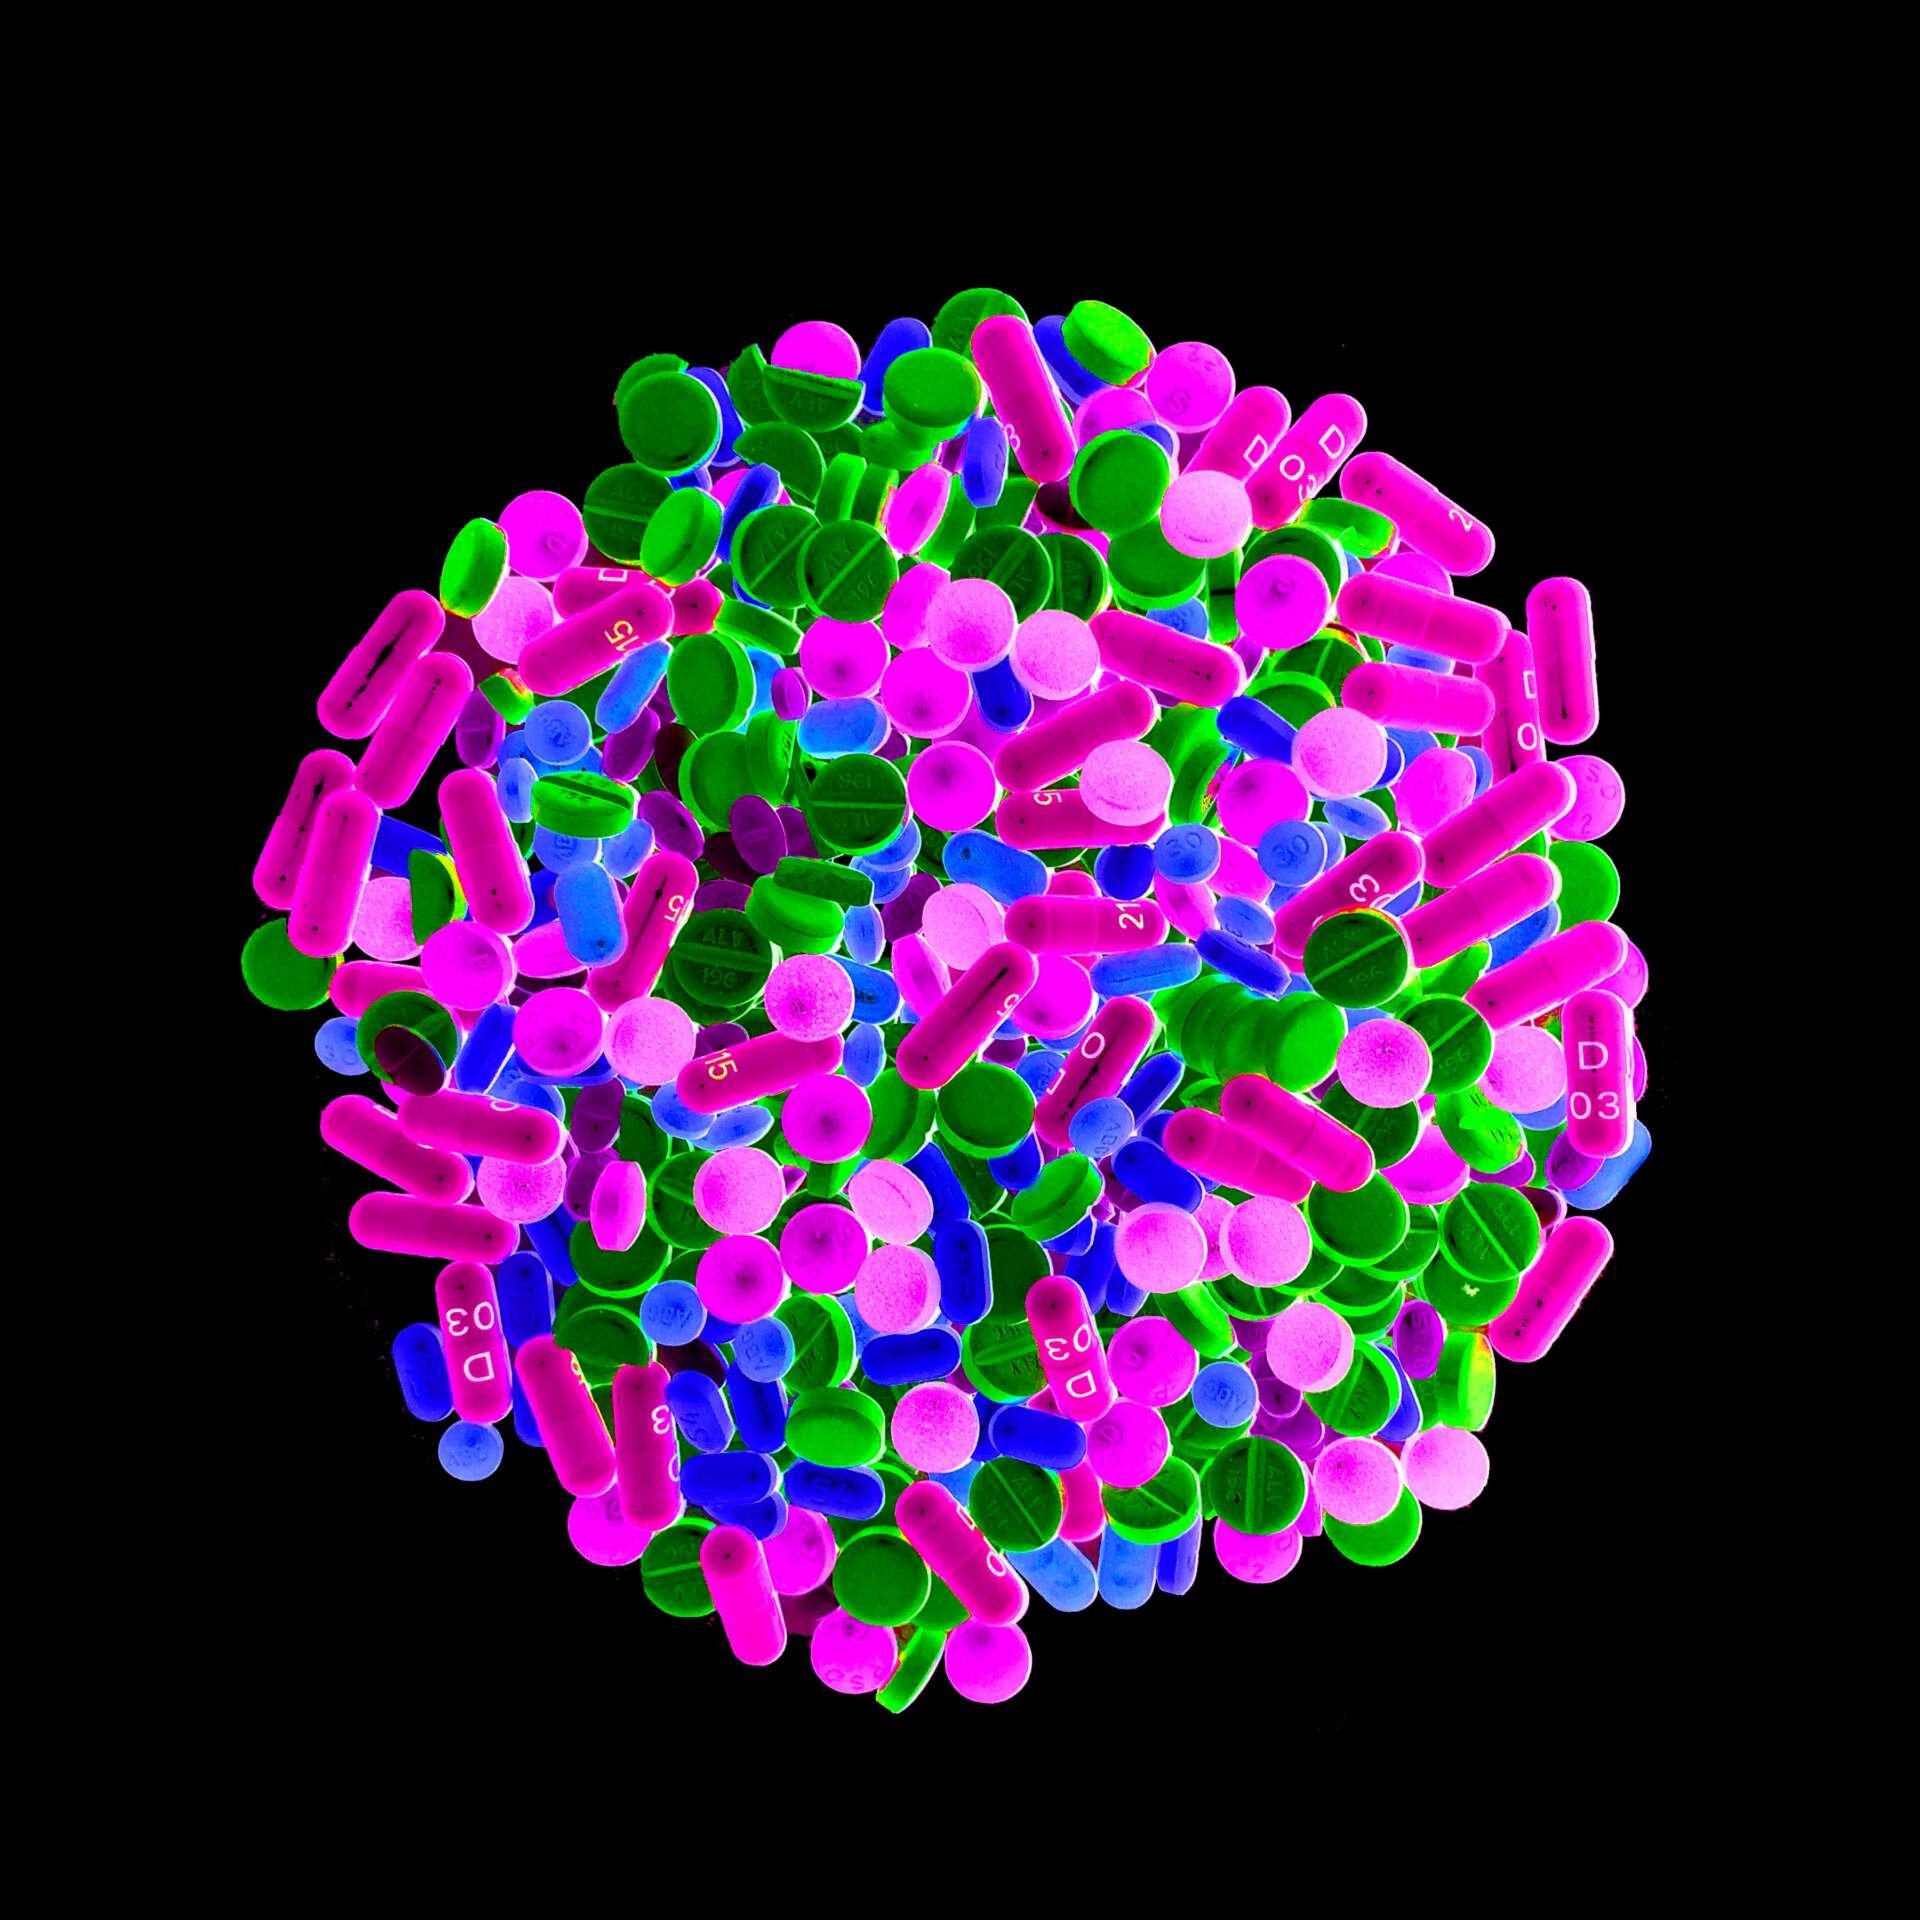

I went through hell(my doctor said so) and I’m alive. I was unlucky enough to have a cancer. I was bed ridden, too weak to create much of anything but I still had ideas firing in my brain. The only thing I had an abundance of were medications, 21 bottles of pills and a myriad of creams, ointments, and powders.

In my frustration I dumped a bunch of those pills out they were pretty, I snapped a pic. The meds I was to discontinue got their farewell by being crushed, I took a pic. I liked it, it made me feel like something other than a patient. I spelled out symptoms with their corresponding pills, sometimes taking hours more pictures.

I had wanted to be one of those cool artists that did photo diaries or Vlogs of the whole illness. I was far too out of it, between the pain and the meds, to even think about doing something like that. With help, I began digitally manipulating them to make them more colorful and textural, it gave me hope amidst the mess.

I was hurting and it helped. Aren’t we all hurting? Each person has their own mess to deal with. Many stop to take a picture of something that causes a stir in them. I want to share what gave me hope through the web of treatments, trauma, and a myriad of medication.